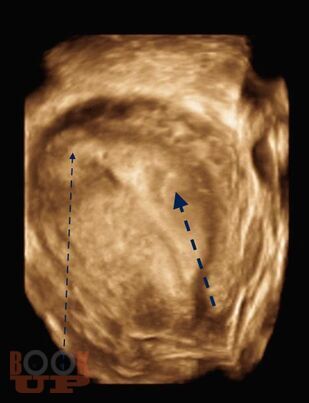

В учебно-методическом пособии приведен сравнительный анализ существующих методов лечения беременности в интерстициальном отделе маточной трубы и ангулярной беременности. Подробно изложен собственный запатентованный протокол лечения интерстициальной трубной беременности в зависимости от данных ультразвукового исследования в совокупности с уровнем ХГЧ в сыворотке крови беременной, разработанный авторами. Данный протокол позволяет на основании полученных диагностических данных выбрать оптимальный метод органосохраняющего лечения, определить методы последующего контроля состояния пациента.